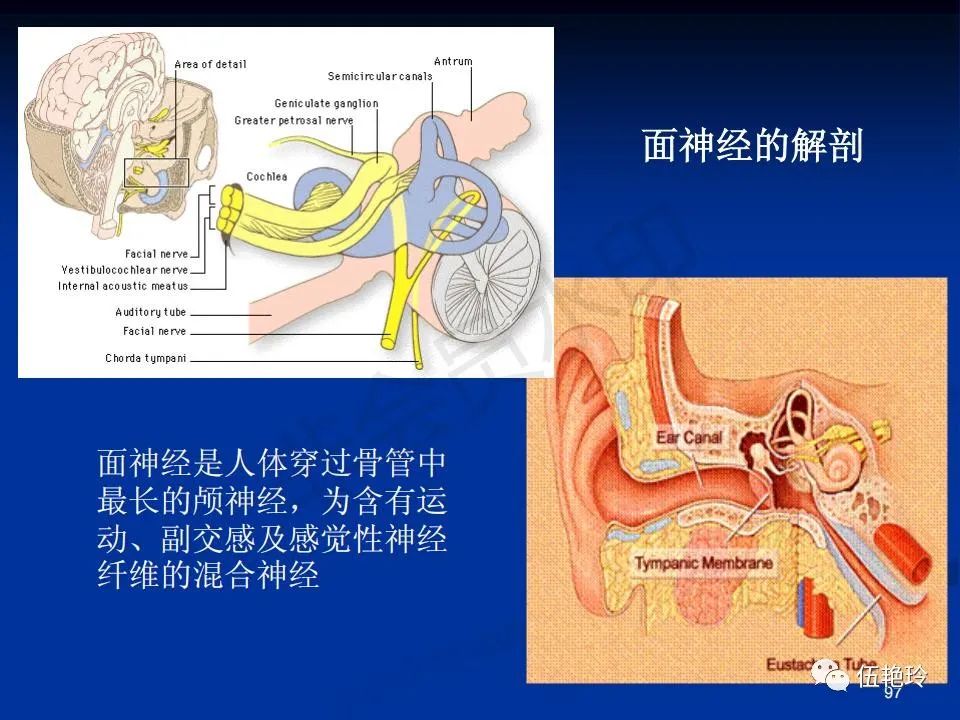

耳与面神经的解剖